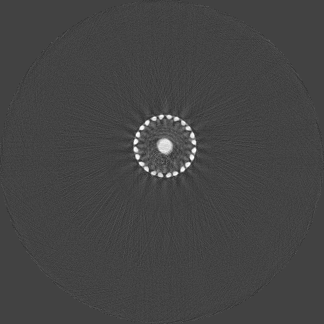

Beam hardening and metal artefacts pose challenges during CT imaging in the presence of metal hardware [17]. This paper presents data that demonstrates the use of spectral imaging in reducing beam hardening effects and metal artefacts. A high-Z sensor layer like CdTe is necessary to provide improved spectral resolution at higher x-ray energies needed for typical implant visualisation. Multi-energy acquisition of metal samples has the added advantage of capturing spectral information which exhibits reduced artefacts and reasonable non-metal (tissue) information. Further, the results were obtained without any hardware filters (except for the intrinsic filter-equivalent in the x-ray tube) and without any numerical corrections. A global reduction in noise due to charge sharing effects was seen due to the availability of CSM. 3D visualisation of the samples (figure 9) revealed finer spatial structures.